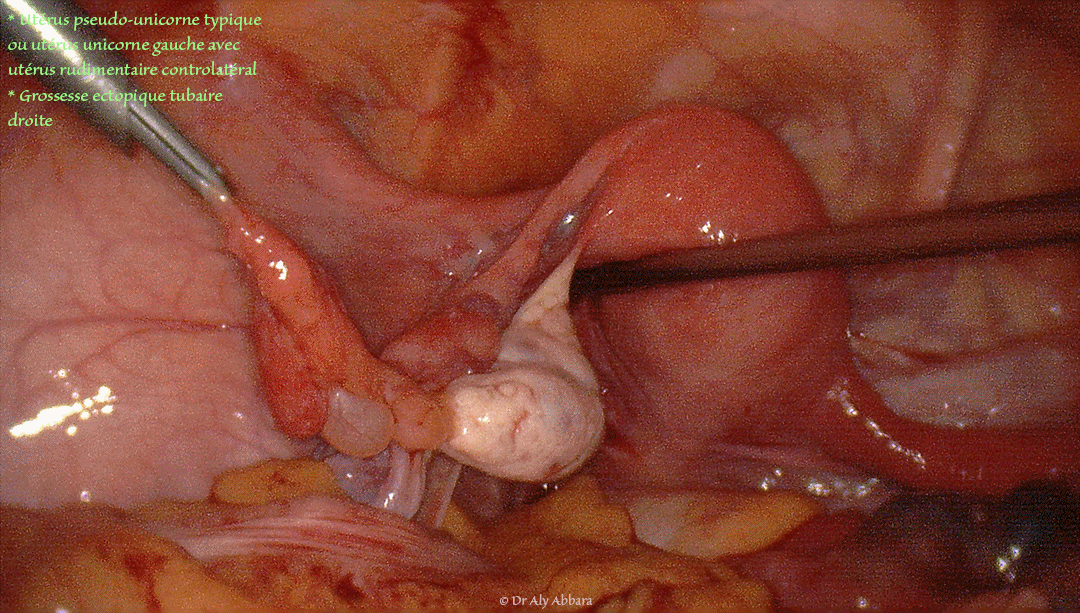

• Images cliniques cœlioscopiques montrant un utérus malformé, pseudo unicorne typique gauche avec corne droite rudimentaire et grossesse extra-utérine tubaire droite (hématosalpinx).

• Sur ces images, on constate la présence :

• annexes utérines gauches normales (trompe et ovaire) ;

• utérus malformé ; il s'agit d'un utérus unicorne gauche relié à une corne utérine rudimentaire controlatéral (d'où le nom de l'anomalie : utérus pseudo-unicorne typique parce que en cas d'utérus uni-corne typique, on ne retrouve pas la corne utérine rudimentaire controlatéral) ;

• la corne utérine rudimentaire droite est ferme, sans cavité, et long d'environ 5 cm ; à son extrémité distale on retrouve les annexes utérines droites qui paraissent anatomiquement normales ;

• l'ovaire droit est relié à la corne rudimentaire par court ligament utéro-ovarien ;

• la trompe droite est le site d'une grossesse ectopique tubaire se manifestant par le développement d'un hématosalpinx dans la portion tubaire moyenne.

• Après la salpingectomie totale droite per-cœlioscopique, on remarque, sur le site de résection du mésosalpinx droit, que cette trompe s'insère normalement sur le ligament large droit.